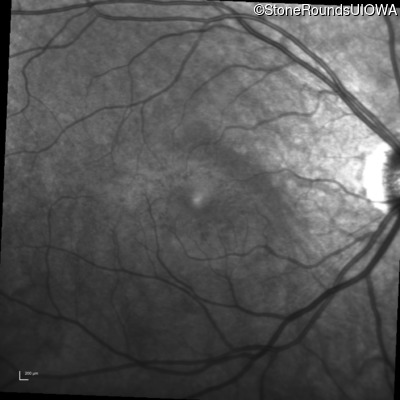

Infrared Fundus Photograph - Right - 20/40 +1

Exemplar

Infrared Fundus Photograph - Left - 20/50